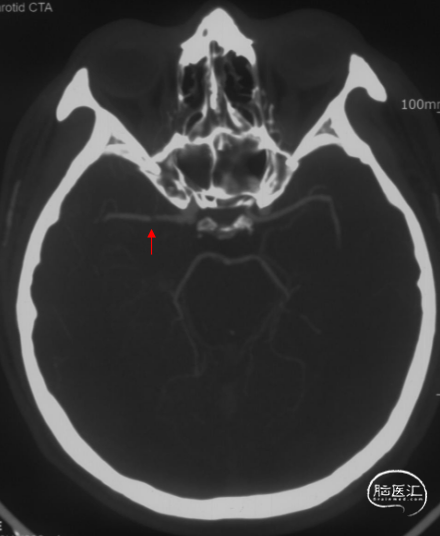

CT显示左侧顶叶低密度水肿影,内见高密度血肿影;上矢状窦高密度,考虑上矢状窦血栓可能大。

MRV可见上矢状窦及右侧横窦充盈缺损。